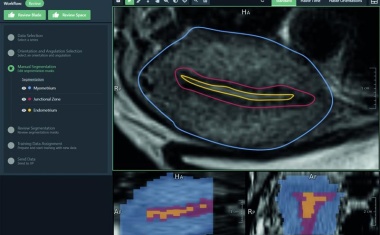

Das Spin-off Plain Medical entstand aus der langjährigen Zusammenarbeit des Fraunhofer-Instituts für Digitale Medizin MEVIS mit dem Radboud University Medical Center (UMC) und hat seine Arbeit im niederländischen Nijmegen im Sommer 2025 aufgenommen.